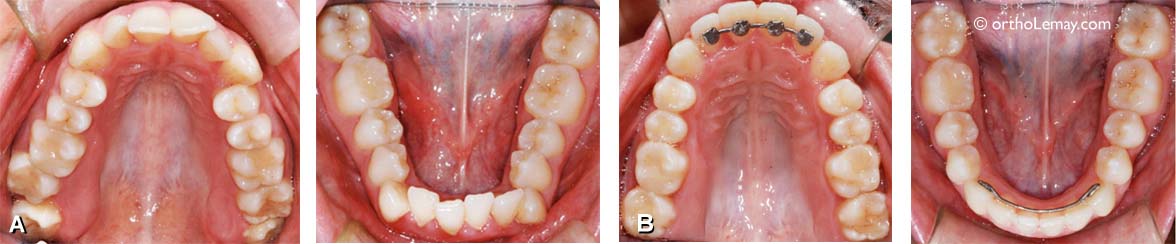

• (A) Condition initiale, lors de la pose  l’appareil d’expansion.

• (B, C) Lors de l’immobilisation de l’appareil, une zone rouge légèrement plus basse apparait sur le bord des incisives centrales (flèches bleues).

• (D) Après quelques semaines, les centrales reviennent vers l’intérieur et cette zone rouge est disparue (A à D sont le même cas).

• (E, F) Autre cas lors de l’immobilisation de l’appareil.

• (G, H) Deux cas différents montrant la zone triangulaire très visible après la fin de l’activation de l’appareil.